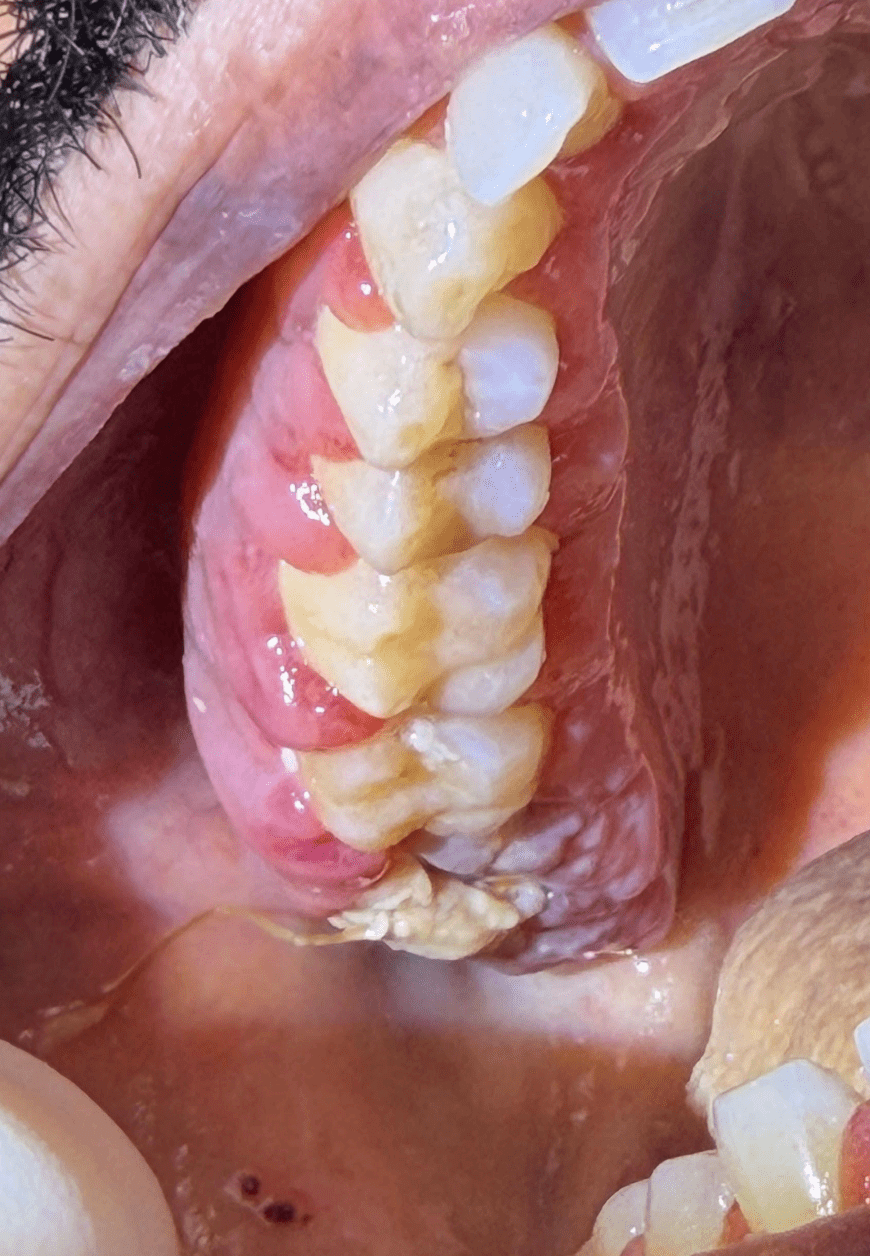

- Progressive edema and erythema of gingiva and extraction sites

- At one week: Ecchymosis and ulcerations were present intra and extraorally

- Spontaneous gingival bleeding and mucosal bleeding[4][2]

- Petechiae and ecchymoses of the oral mucosa[4][2][5]

- Oral ulcerations and mucosal pallor[4][2][5]

- Ecchymosis and oral ulcerations developing postoperatively, especially when progressive, may indicate underlying thrombocytopenia or coagulopathy from hematologic malignancy[3][5][20]